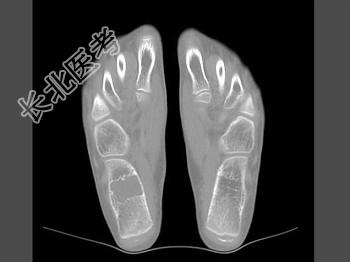

- 单项选择题女,15岁, 间歇性足跟痛,结合图像, 最可能的诊断是 ( )

A、骨囊肿

B、骨巨细胞瘤

C、骨髓瘤

D、骨纤维异常增殖症

E、动脉瘤样骨囊肿